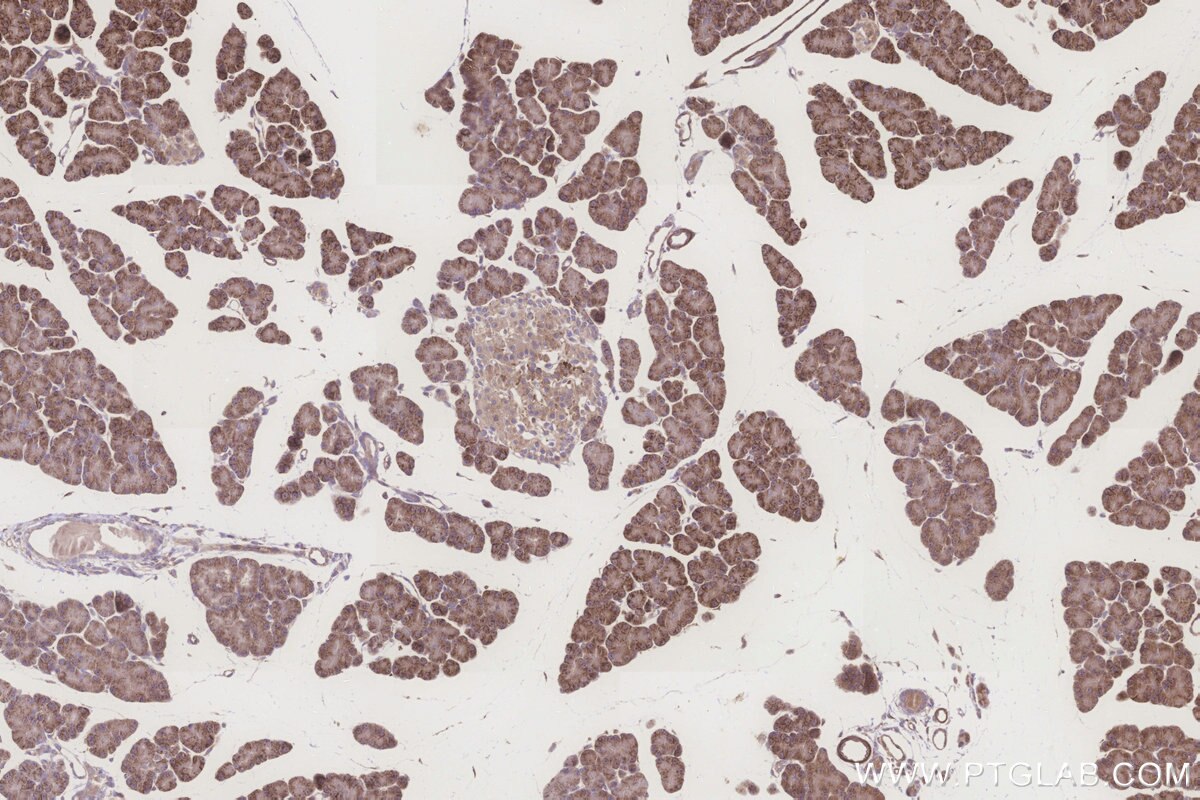

Validation Data Gallery

KHC3260 is a ready-to-use IHC kit for staining of ALDH1L2. The kit provides all reagents, from antigen retrieval to cover slip mounting, that require little to no diluting or handling prior to use. Simply apply the reagents to your sample slide according to the protocol and you're steps away from obtaining high-quality IHC data.